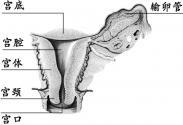

子宫肥大

628健康网为您分享有关子宫肥大的症状,子宫肥大的治疗方法,子宫肥大的预防知识,子宫肥大的症状图片,子宫肥大吃什么药,子...

子宫发育异常

628健康网为您分享有关子宫发育异常的症状,子宫发育异常的治疗方法,子宫发育异常的预防知识,子宫发育异常的症状图片,子...